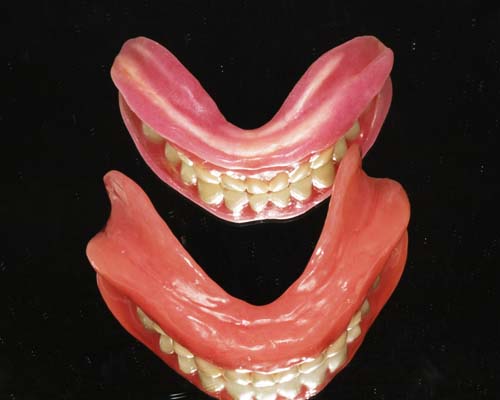

入れ歯の形で違いがわかる

写真の入れ歯の上と下とでは随分形が違いますが、両方とも同じ人の下の入れ歯です。どちらが良いのか、最初は私も全くわかりませんでした。実は多くの歯科医師も、入れ歯の勉強を相当しないと判断ができません。

歯を1個1個並べていく

人工歯は、1本1本並べていきます。既に歯は無くなっていますので、お口の中の形からどこに並べるかを想像するしかありません。とても重要な作業もあり、非常に難しい作業でもあります。10人の歯科医がいれば10通りの歯並びができるといっても過言ではありません。

噛み合わせ・審美性・話しやすさ

すべてに配慮

人工歯を並べる位置は患者さんごとに異なります。そのため、人工歯は1本ずつ分かれていて、自由に配置できるようになっているのです。術者の知識と技術がもっとも必要とされる作業です。患者さんに満足して頂ける入れ歯を作るには(1)噛み合わせ (2)審美性 (3)話しやすさをすべて満たさなければなりません。これらを総合的に配慮しながら入れ歯を作ることで、より元の歯に近い噛み心地を提供できるのです。